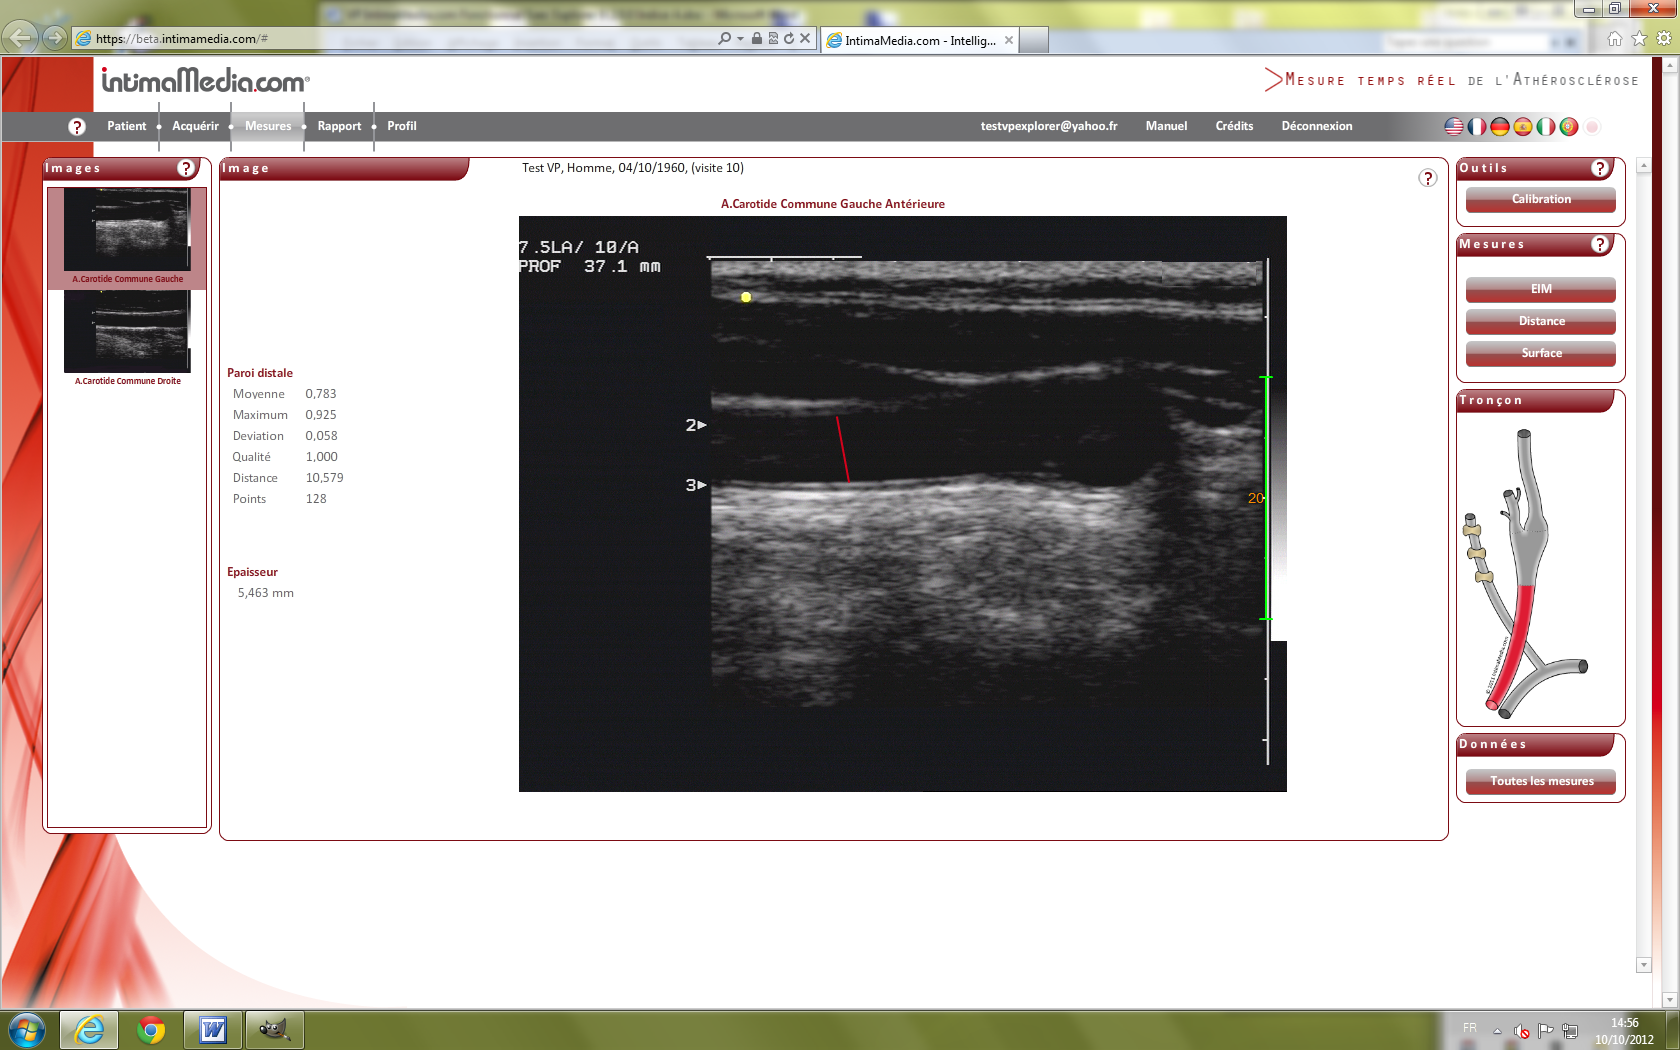

Images VP IExplorer 9. IntimaMedia 2.0.0 Fonctionnal

Test37.png